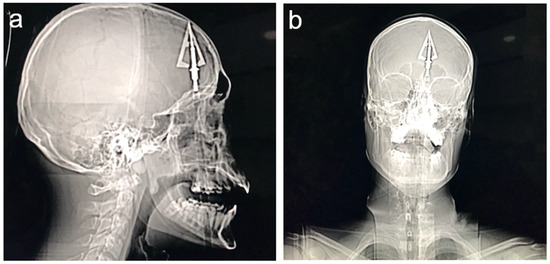

2.1. Clinical Presentation

| Current case | 2024 | Poland | 1 | 20 | M | suicide attempt | crossbow | transmental | CT | surgical | ENT surgeon | yes | olfactory dysfunction | |